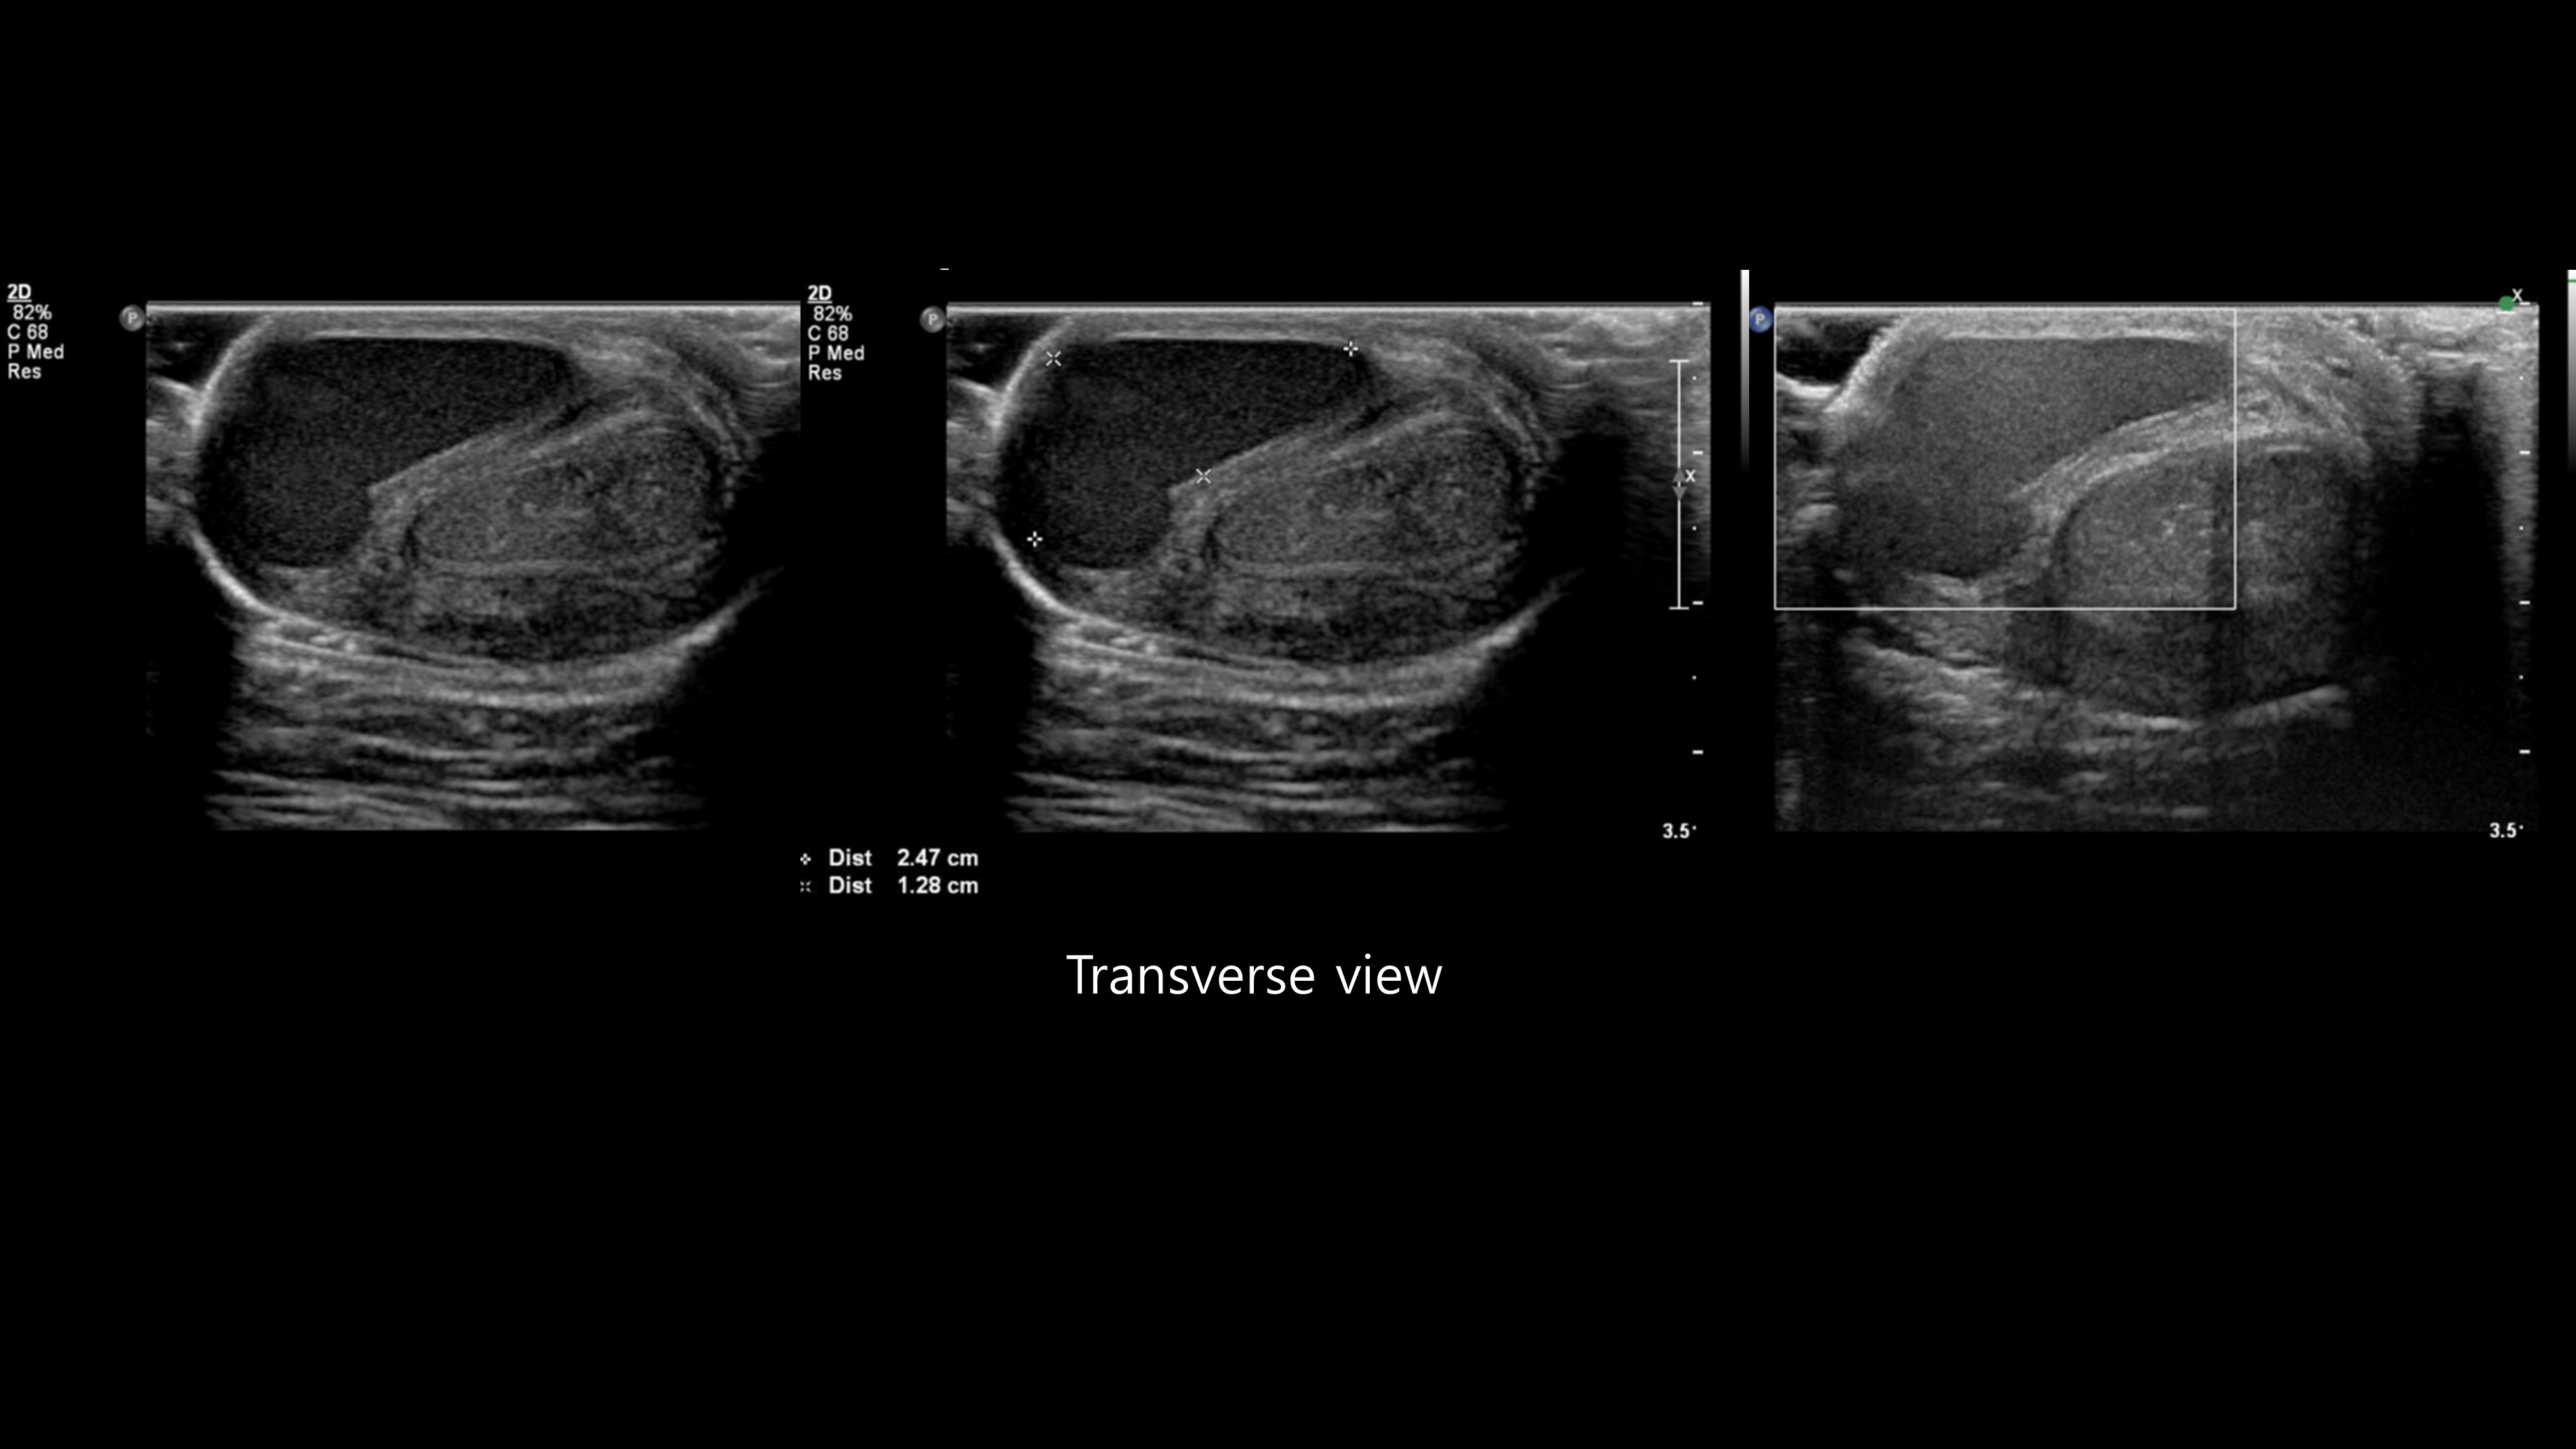

[350,Genitourinary [GU]] 18/M,Palpable penile mass

Genitourinary [GU]

US,

What is the best diagnosis?